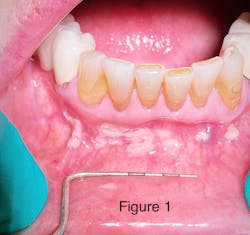

Take a look at the initial photograph. What’s the first thing that comes to your mind? Scattered, white, creamy patches in the lower anterior vestibule, each measuring approx. 3–6 mm (figure 1). Now, take a look at the second picture after the white patches were easily wiped off with gauze (figure 2). Note the red, thin membraned tissue? It was very tender to the touch.This diagnosis should be a slam dunk by now. Yup, you guessed it. Good ol’ pseudomembranous candidiasis, aka thrush.

- Acute pseudomembranous candidiasis consists of creamy, loose patches of desquamative epithelium that are easily removed.1 Red tissue tender to the touch is what is painful to the patient.